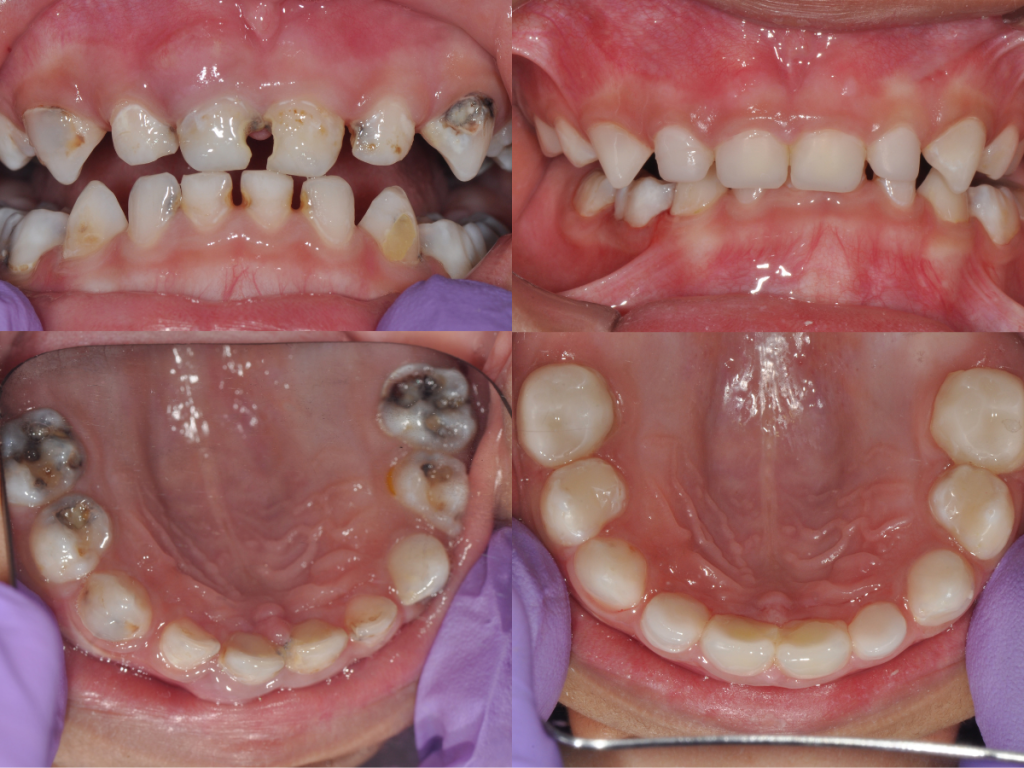

Esthétique naturelle et ajustement parfait

La teinte blanche naturelle et la surface brillante de Ceramir Pediatric Crown offrent une intégration harmonieuse dans la bouche de l’enfant.

Les coiffes sont préformées pour reproduire fidèlement la morphologie des dents temporaires et sont disponibles en plusieurs tailles (S, M, L, XL).

Elles se réparent facilement en bouche à l’aide d’un composite photopolymérisable et s’ajustent sans meulage de la dent antagoniste.

Ceramir Pediatric Crown s’adresse à de nombreuses situations cliniques :

– Caries précoces de l’enfance (CPE)

– Hypominéralisations molaires (HSPM)

– Anomalies de structure (amélogénèse, dentinogénèse imparfaites)

– Fractures, abrasions, érosions

– Restauration complète de dents temporaires délabrées